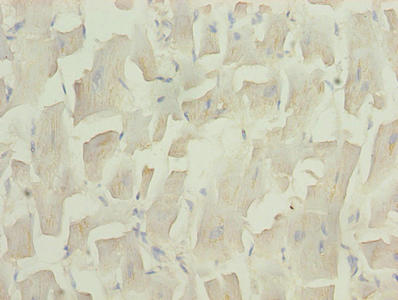

Immunohistochemistry of paraffin-embedded human skeletal muscle tissue using CSB-PA025556LA01HU at dilution of 1:100

Immunohistochemistry of paraffin-embedded human heart tissue using CSB-PA025556LA01HU at dilution of 1:100